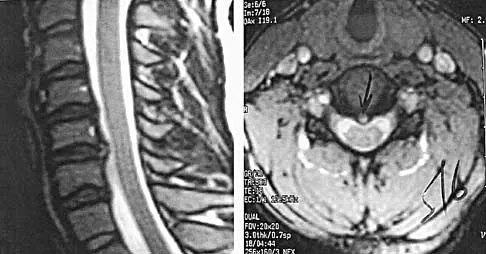

A 65-year-old man with ankylosing spondylitis has neck pain after falling back over his lawnmower, striking his thoracic spine, and forcing his neck into extension. Examination reveals subtle weakness of the intrinsics and finger flexors at approximately 4+/5. Initial management consists of immobilization in a rigid collar, and placing his head in the anatomic position. Radiographs reveal a subtle extension fracture of the lower cervical spine. Approximately 6 hours after the injury, he reports increasing paresthesias in his upper and lower extremities, and examination now shows his intrinsics are 2/5, finger flexors are 3/5, and his triceps are now weak at 4/5 on manual motor testing. In addition, his lower extremities now show weakness in both dorsal and plantar flexion of the ankle in the range of 4/5. Repeat radiographs appear unchanged. An MRI scan is shown in Figure 2. Management should now consist of